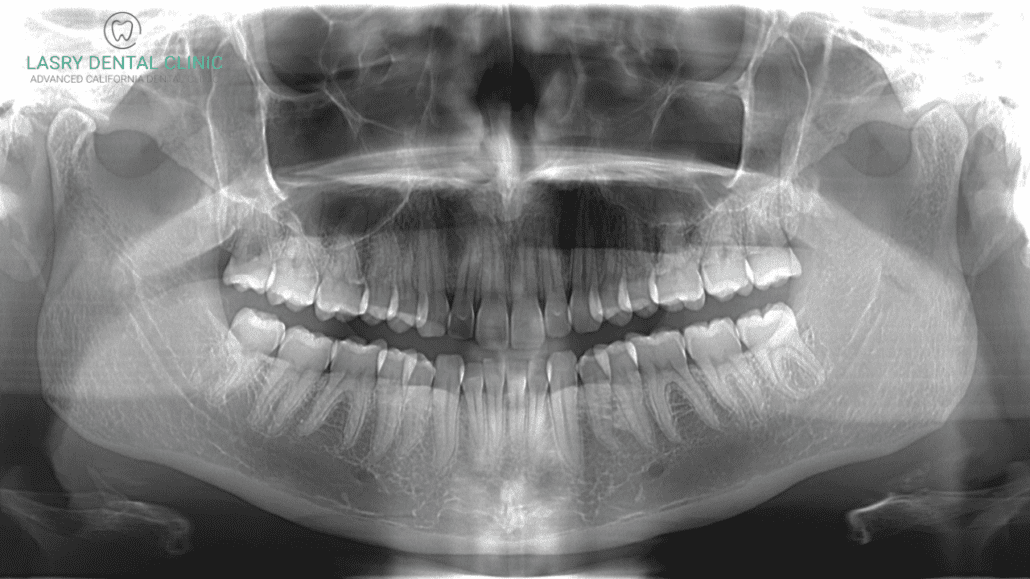

The production of dental CT (Cone Beam Computed Tomography) scanners in China—particularly by ISO 13485-certified manufacturers like Carejoy Digital—follows a tightly controlled, traceable, and audited workflow designed for medical device compliance and long-term durability.

2. Sensor Calibration & Imaging Accuracy

At the core of every dental CT scanner is the X-ray detector and sensor array. Carejoy Digital maintains an on-site Sensor Calibration Laboratory that performs:

- Pixel Gain & Offset Calibration: Performed at multiple kV/mA settings to correct for sensor non-uniformity

- Geometric Calibration: Ensures sub-10µm spatial accuracy using calibrated phantoms (e.g., aluminum sphere arrays)

- Dose Linearity Testing: Validates ALARA (As Low As Reasonably Achievable) compliance across exposure ranges

- AI-Driven Artifact Correction: Real-time software compensation for scatter, beam hardening, and motion artifacts